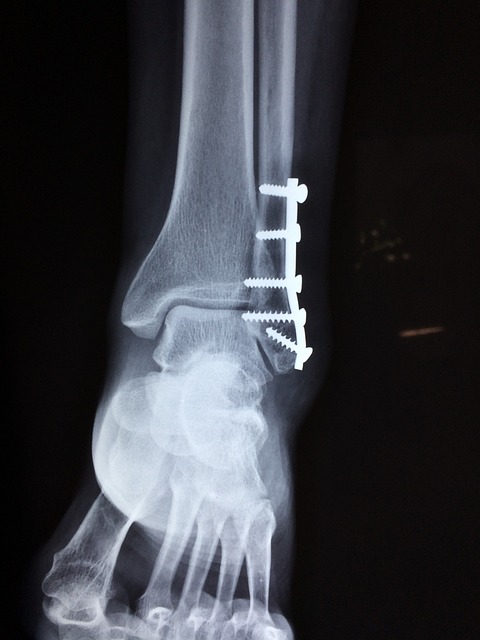

하지만 골절이 발생하면 문제가 커집니다. 골다공증으로 인해 골절이 잘 발생하는 부위는 손목, 척추, 대퇴골입니다. 특히 척추 골절은 증상이 나타나기까지 시간이 걸릴 수 있는데, 키가 작아지거나 등이 구부러지면서 골절을 알게 되는 경우가 많습니다.

1) 이중 에너지 X선 흡수계측법(DXA)

가장 많이 쓰이는 진단 방법으로, 두 개의 X선을 활용해 뼈가 얼마나 X선을 흡수하는지를 분석하여 뼈 밀도를 계산합니다.